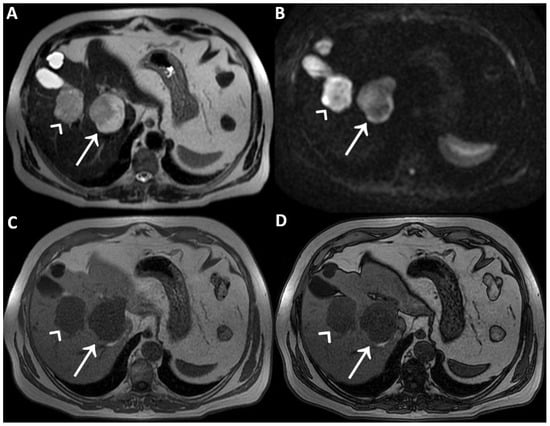

On T2WI without fat-suppression (A) and with fat-suppression (B) acquired a few days later without previous contrast agent administration; the lesions’ hyperintensity was clearly homogeneous. Therefore, the inhomogeneous signal intensity of the lesions on post-contrast T2WI is a pseudo-inhomogeneity caused by limitations of the acquisition protocol and a direct consequence of the contrast-induced reduction in the hydrogen nuclei relaxation time. Consequently, it was possible to establish the lesions’ benignity and make the final diagnosis of cavernous hemangiomas.